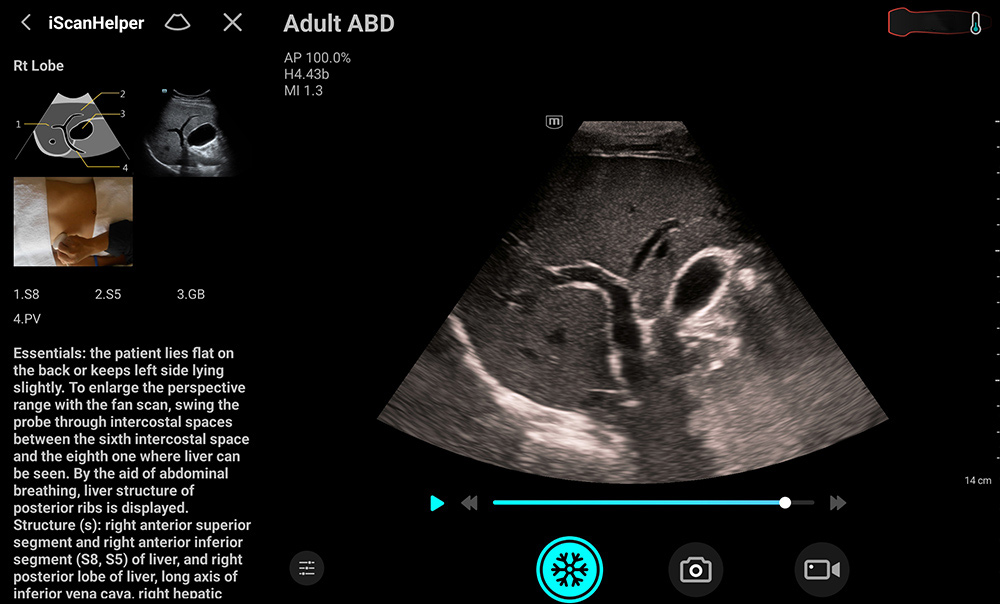

1Facile da usare, con un'interfaccia utente intuitiva

2Migliora l'efficienza grazie alla possibilitĂ di utilizzo con una sola mano